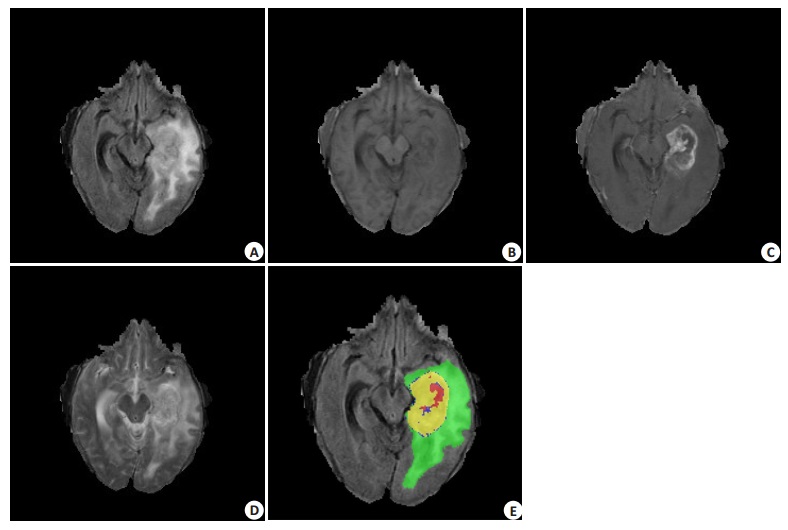

1 资料和方法 1.1 实验数据我们使用2015年多模态脑肿瘤分割挑战赛[2](BraTS)的数据进行训练和测试。BraTS是一个全球性质的比赛,其训练集包括220例高级别胶质瘤与54例低级别胶质瘤及对应的组织分割图像。测试集包括110例胶质瘤数据,但未提供更详细的肿瘤分级与对应的分割图像。脑胶质瘤(图 1F)共分为以下4类:(1)显示为红色区域的坏死组织;(2)显示为绿色区域的水肿;(3)显示为蓝色区域的未增强肿瘤;(4)显示为黄色区域的增强肿瘤。为了评估分割的优劣,4中不同的组织被组合成3个集合:(1)整个肿瘤,即所有类;(2)肿瘤核心区,由坏死组织、未增强肿瘤和增强肿瘤组成;(3)肿瘤增强区,仅由增强肿瘤组成。测试集是不公开的,仅能采用在线上传的评估方式(https://www.smir.ch/BRATS/Start2015)。每个病例包括Flair(图 1A)、T1(图 1B)、T1增强(图 1C)、T2(图 1D)共4种MRI模态。它们是由多达19种不同的扫描设备配置和机构提供。MRI数据均配准至相同的图像空间并去除头骨部分。每个图像的大小为240×240×155,分辨率重采样至1 mm×1 mm×1 mm,且所有的图像标签均由1至4个专家手动分割。

图 1 BraTS2015数据集的例子 Figure 1 The CaseinBraTS2015 dataset. A: Flair; B: T1: C: T1 enhanced image; D: T2 and (E) the corresponding expert segmentation result. |